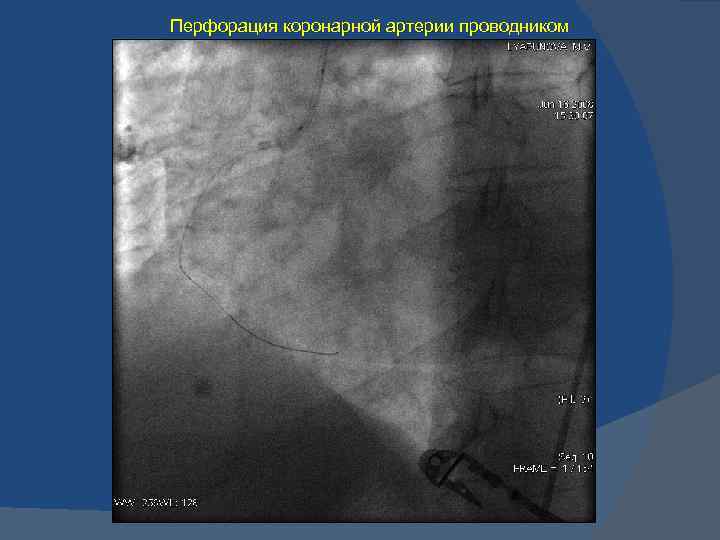

Хроническая окклюзия артерий: причины, симптомы и лечение